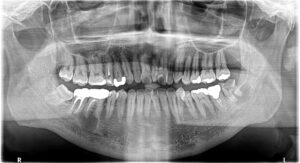

今回の患者さんは大きな病変が2つ、小さい病変が1つありました。

右下6番目と左下8番目の歯にウズラの卵くらいの大きな病変があります。右上6番にも小さな病変があります。

上の写真の赤丸が根尖病変です。